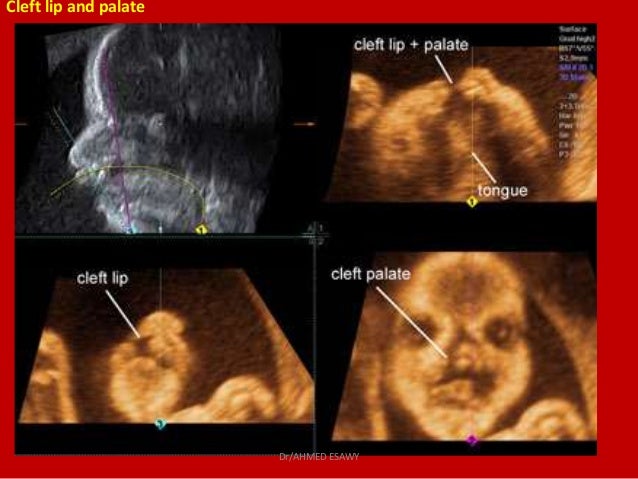

Складка на узи

Складка на узи 114 фото